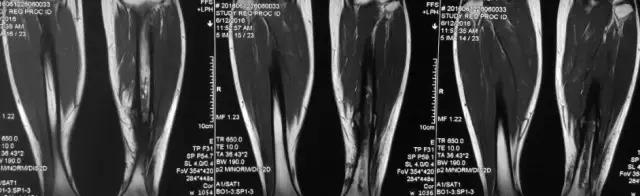

影像检查

诊断:感染。 检查:膝关节MRI,确认伤口窦道是否与髓腔相通。 治疗:1、血沉和C反应蛋白正常,目前无需特殊处理。 2、如果窦道反复出现或血沉和C反应蛋白升高可考虑手术。如证明窦道与髓腔相通,需行扩髓。

1、诊断:感染。(如果窦口与髓腔相通就是骨感染) 2、检查中血沉和要动态检查。如果局部红肿伴胀痛就查。 3、如果扩髓需要远近端开口。